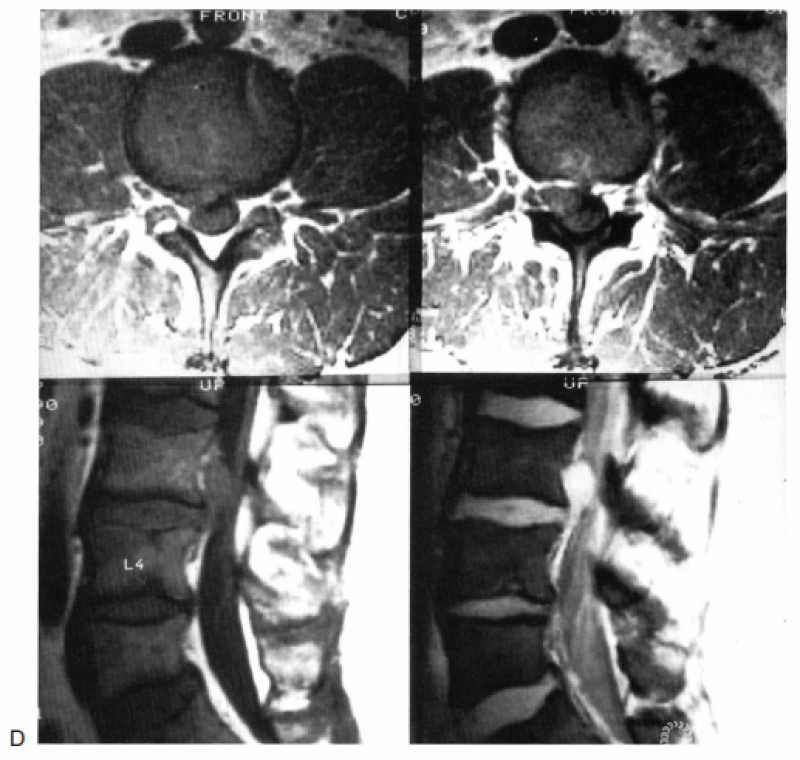

以椎弓根下缘作为虚拟的分割线,每个解剖节段如同一幢楼房一样可分为3层(这个概念非常清楚易懂)。接下来对各层进行判读,这样外科医生可以很准确地定位病变在椎间盘/椎体柱与神经柱间的具体位置。图18.8-18.10所示为各层病变的举例。

图18.10 A:图示为第2层的椎间盘突出,以椎间孔内的突出最为常见。箭头所示为椎间盘突出的移位路径;B:T1加权轴位MRI显示L3右侧椎间孔内的椎间盘突出(箭头);C:罕见的第2层椎间盘突出,位于椎管内。箭头所示为椎间盘突出的移位路径;D:T1加权轴位(上图)和矢状位(左下图)以及梯度回波矢状位(右下图)MRI显示第2层椎间盘突出